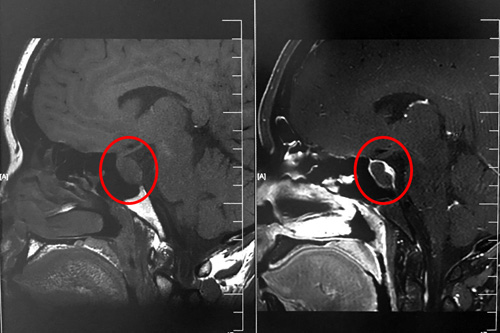

术前影像显示:垂体占位,不排除垂体瘤囊性变

这时,从患者影像资料上来看,颅内鞍区的肿物大小为1.3cm*2cm*0.8cm,可以确认是鞍区良性肿瘤,垂体瘤囊变的可能性较大,有压迫视神经的迹象。性激素检查发现患者垂体泌乳素分泌很高,超出参考值范围55个单位。占位引起高颅压,压迫神经,造成患者额头和两侧颞部疼痛明显,眼睛也出现胀痛症状,已严重影响到其生活。各位专家会诊结果:垂体瘤囊变符合手术指征,应尽快安排手术。做了手术会尽快解除压迫,垂体激素分泌也会逐步回归正常。